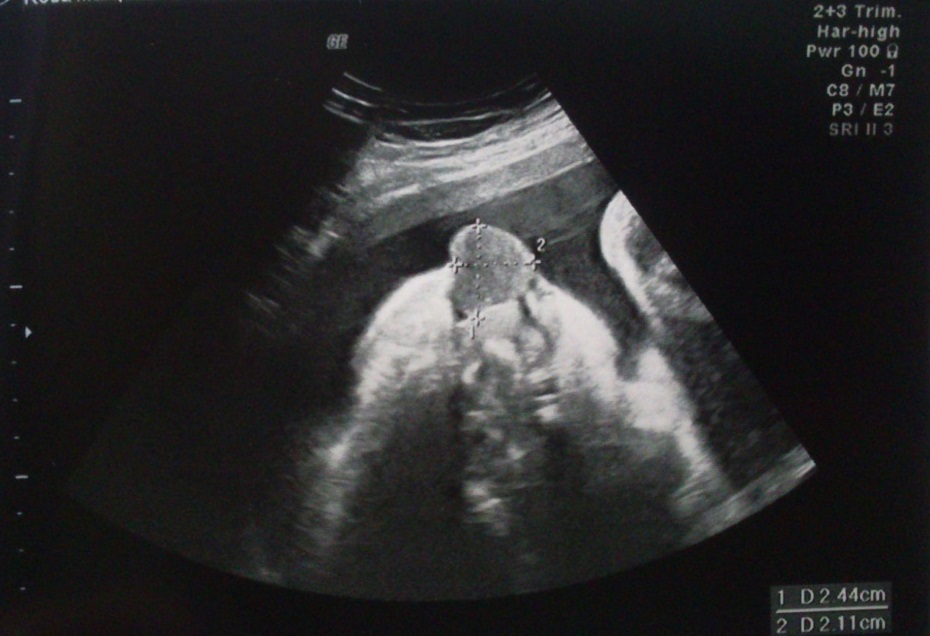

Descreve-se um caso clínico de ECCG com diagnóstico em ecografia prénatal (33 semanas de gestação). Recém-nascido de termo, parto eutócico, género feminino, sem necessidade de manobras de reanimação. Apresentava volumosa massa procidente da arcada alveolar superior, sem compromisso da via aérea ou da deglutição. Excisão cirúrgica sob anestesia geral nas primeiras 24 horas de vida. Confirmação diagnóstica de ECCG após avaliação anatomo-patológica com imunohistoquimica. Reavaliação aos dois meses de vida sem recidiva ou outras complicações.